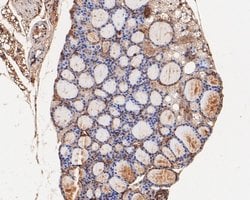

Invitrogen™ RhoGDI Polyclonal Antibody

RhoGDI Polyclonal Antibody for Western Blot, IHC (P)

| Applications | Immunohistochemistry (Paraffin), Western Blot |